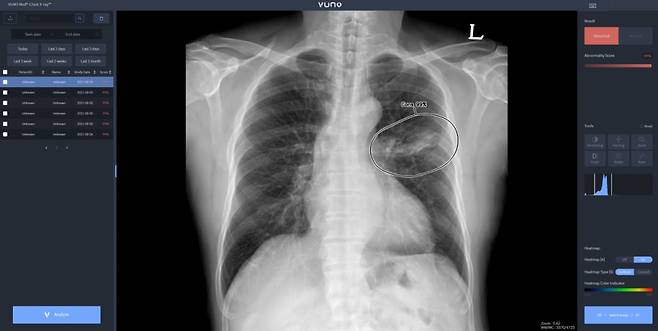

우즈베키스탄 군 병원에 도입된 솔루션은 뷰노의 AI 기반 상지 엑스레이 판독 보조 솔루션 '뷰노메드 익스트리미티 엑스레이'와 이동형 엑스레이 장비에 AI 기반 흉부 엑스레이 판독 보조 솔루션 '뷰노메드 체스트 엑스레이'를 탑재한 패키지 제품이다.

우즈베키스탄 군 병원에 도입된 솔루션은 뷰노의 AI 기반 상지 엑스레이 판독 보조 솔루션 '뷰노메드 익스트리미티 엑스레이'와 이동형 엑스레이 장비에 AI 기반 흉부 엑스레이 판독 보조 솔루션 '뷰노메드 체스트 엑스레이'를 탑재한 패키지 제품이다. 두 제품 모두 뷰노가 과학기술정보통신부 및 정보통신산업진흥원(이하 NIPA)이 추진하는 '군 의료영상 데이터 기반 인공지능 판독 시스템 고도화 및 실증 사업(이하 군 의료 사업)'의 일환으로 개발한 제품이다. 격오지를 중심으로 현장 의료서비스가 가능하도록 설계돼 의료 인프라가 낙후한 지역에서도 진단 편차를 줄이고 의료진의 진단 효율성을 높일 수 있다.

이번에 공급한 뷰노의 '뷰노메드 익스트리미티 엑스레이'는 딥러닝을 기반으로 X선 영상을 분석해 군 장병들의 부상이 잦은 손목, 손, 아래팔, 팔꿈치, 어깨, 위팔뼈 등 6개 부위의 이상 유무와 위치 정보를 제공하는 인공지능 소프트웨어다. 이동형 엑스레이 장비에 '뷰노메드 체스트 엑스레이'를 탑재한 패키지 제품은 별도의 차폐 시설 없이도 다양한 상황에서 환자의 흉부 X선 촬영 후 수 초 이내에 판독 결과를 제공할 수 있다.